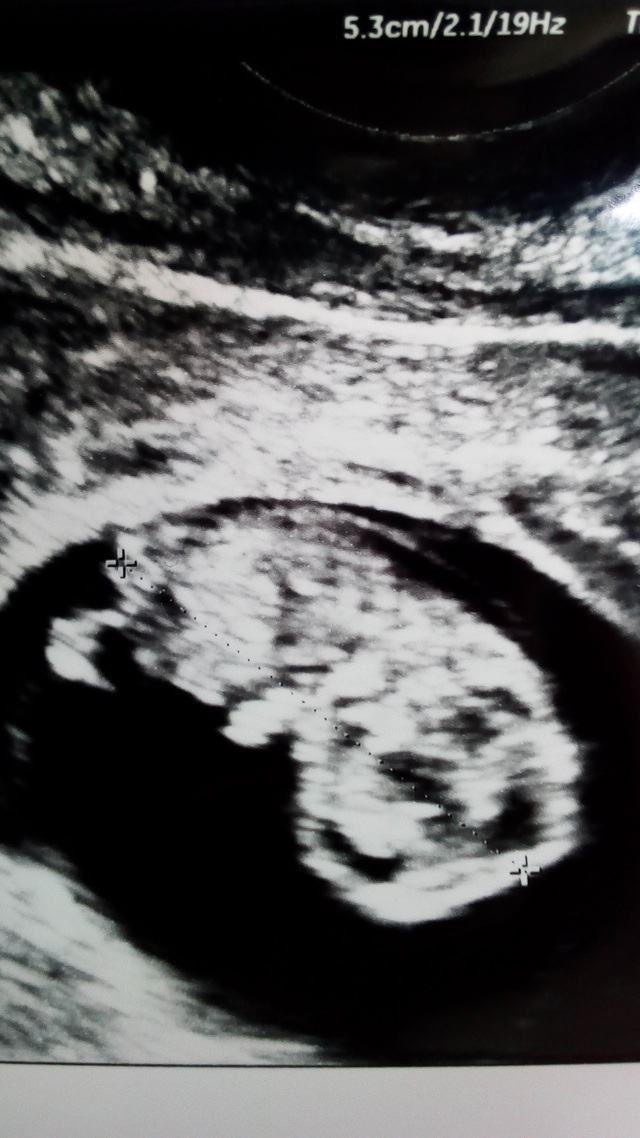

9週0日(9w0d・女の子)|nekonie さん(26歳)

エコー写真撮影時のエピソード:

少し見にくいかもしれませんが、よく見ると手をXの形にしているように見えます。

こんなに小さい時から、こんなポーズをしているのはなかなか見れないんじゃないかと思い、家族や友達に見せたらみんなびっくりしていました。キューピーちゃんみたいでとてもかわいくて、一番思い入れのあるエコー写真です。